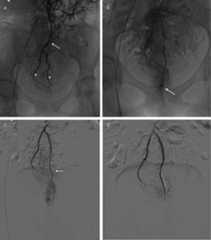

In 2006 the World Conference of Interventional Oncology took place in Cernobbio in front of the picturesque view of the Lake Como in northern Italy, and a new field of medicine was born. At that time, the term “Interventional Oncology” assembled the different techniques and new therapeutic concepts for cancer that had been developing with Interventional Radiology under a discipline that was subsequently integrated into the modern approach for oncologic patient care. We are aware nowadays of the role of the percutaneous ablation therapies and chemo- and radio-embolizations in the therapeutic algorithms for cancer care. In the last few years a more innovative concept is appearing, well explained in some recent cutting-edge reviews published in radiologic and clinical journals [31,32,33]: the interventional immuno-oncology (IO). Curiously, the acronym IO is already used by both radiologists and oncologists to refer respectively to interventional radiology and immuno-oncology. The meeting between these two disciplines is becoming a promising field of innovation for the mini-invasive, patient-specific approach to neoplastic pathology therapy, able to maximize the efficacy of percutaneous tumor ablation therapies and improve the systemic immunologic response to the residual neoplastic cells. The phenomenon, whereby a locally applied therapy triggers a distal antitumor response, is termed the abscopal effect [31,33]. The different techniques, radiofrequency (RF), microwave (MWA), cryoablation, focused ultrasound (FUS), and embolization, variably induce tissue necrosis, thus exposing the tumoral antigens to the immune system and stimulating the physiologic immune response. Specific in-animal trials have assessed the potential of each ablative therapy for interacting with the immunologic processes [34,35,36,37,38]; for instance, among the different ablative percutaneous solutions, cryoablation seems to have the best potential, so much so that some authors have referred to it in terms of “in-vivo dendritic cell vaccine” to highlight the effective impact on the immunologic mechanisms. Several different elements (intracellular organs, antigens, damage-associated molecular patterns DAMPs) are released after the tumoral necrosis and phagocytized by the dendritic cells (DC) activating the complex pathways of the immune response (nuclear factor kappa-light-chain-enhancer of activated B cells, NF-κβ; Heat Shock Protein 70; chemokines, like the Monocyte Chemoattractant Protein-1, CXCL16; cytokines like the TNF-α, IL-1, & IL-16; danger signals such as ATP, cal-reticulin, HMGB1). Oncologists have already adopted immunotherapy to activate and enhance the physiologic response; immuno-modulating drugs are largely divided in two classes, respectively targeting the innate immune system and the adaptive response. New pharmaceuticals are, for instance, the inhibitors of the “check-points” that prevent the inappropriate activation of a cell-mediated immune response (adaptive), such as the Ipilimumab used in metastatic melanoma, the PD-1 inhibitors (Pembrolizumab, Nivolumab, Durvalumab, Avelumab) approved for the treatment of melanoma, renal cell carcinoma, bladder cancer, non-small cell lung cancer, Hodgkin lymphoma, Merkel cell carcinoma and solid tumors. Combination of these new drugs targeting both the adaptive and innate immune system with ablative treatments has been tested in animal models, showing improvement of mean survival, cytolytic activity, tumor-specific T cell activation and dendritic cell maturation. The progressive advances in the understanding of the interactions between interventional therapies and the immune response will advance future clinical applications of interventional immuno-oncology and offer an exciting field of innovation for interventional radiologists (Figure4).

Figure 4.

Interventional management of a renal mass in an inoperable patient, combined approach: transarterial preoperative embolization is performed through femoral access(b) using selective catheterization(c) and injection of glue(d), thus obtaining devascularization before percutaneous ablation.(e) CT-guided cryotherapy; combination of the percutaneous ablative therapies and the immune-modulating drugs in the so-called “Interventional Immunooncology” becomes an unexplored field of application with a tremendous potential to investigate in the next future.